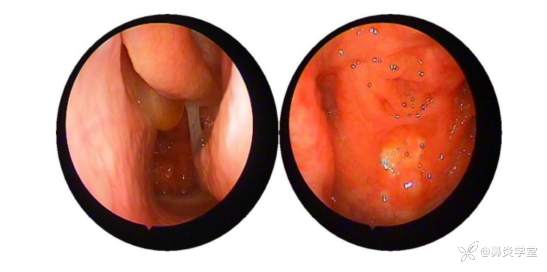

鼻内镜:双侧嗅裂息肉,鼻咽部粘膜光滑。

本例患者鼻内镜检查(见息肉)、鼻窦 CT(提示鼻窦炎),支持慢性鼻窦炎伴鼻息肉诊断。主要鉴别诊断如下[5]: